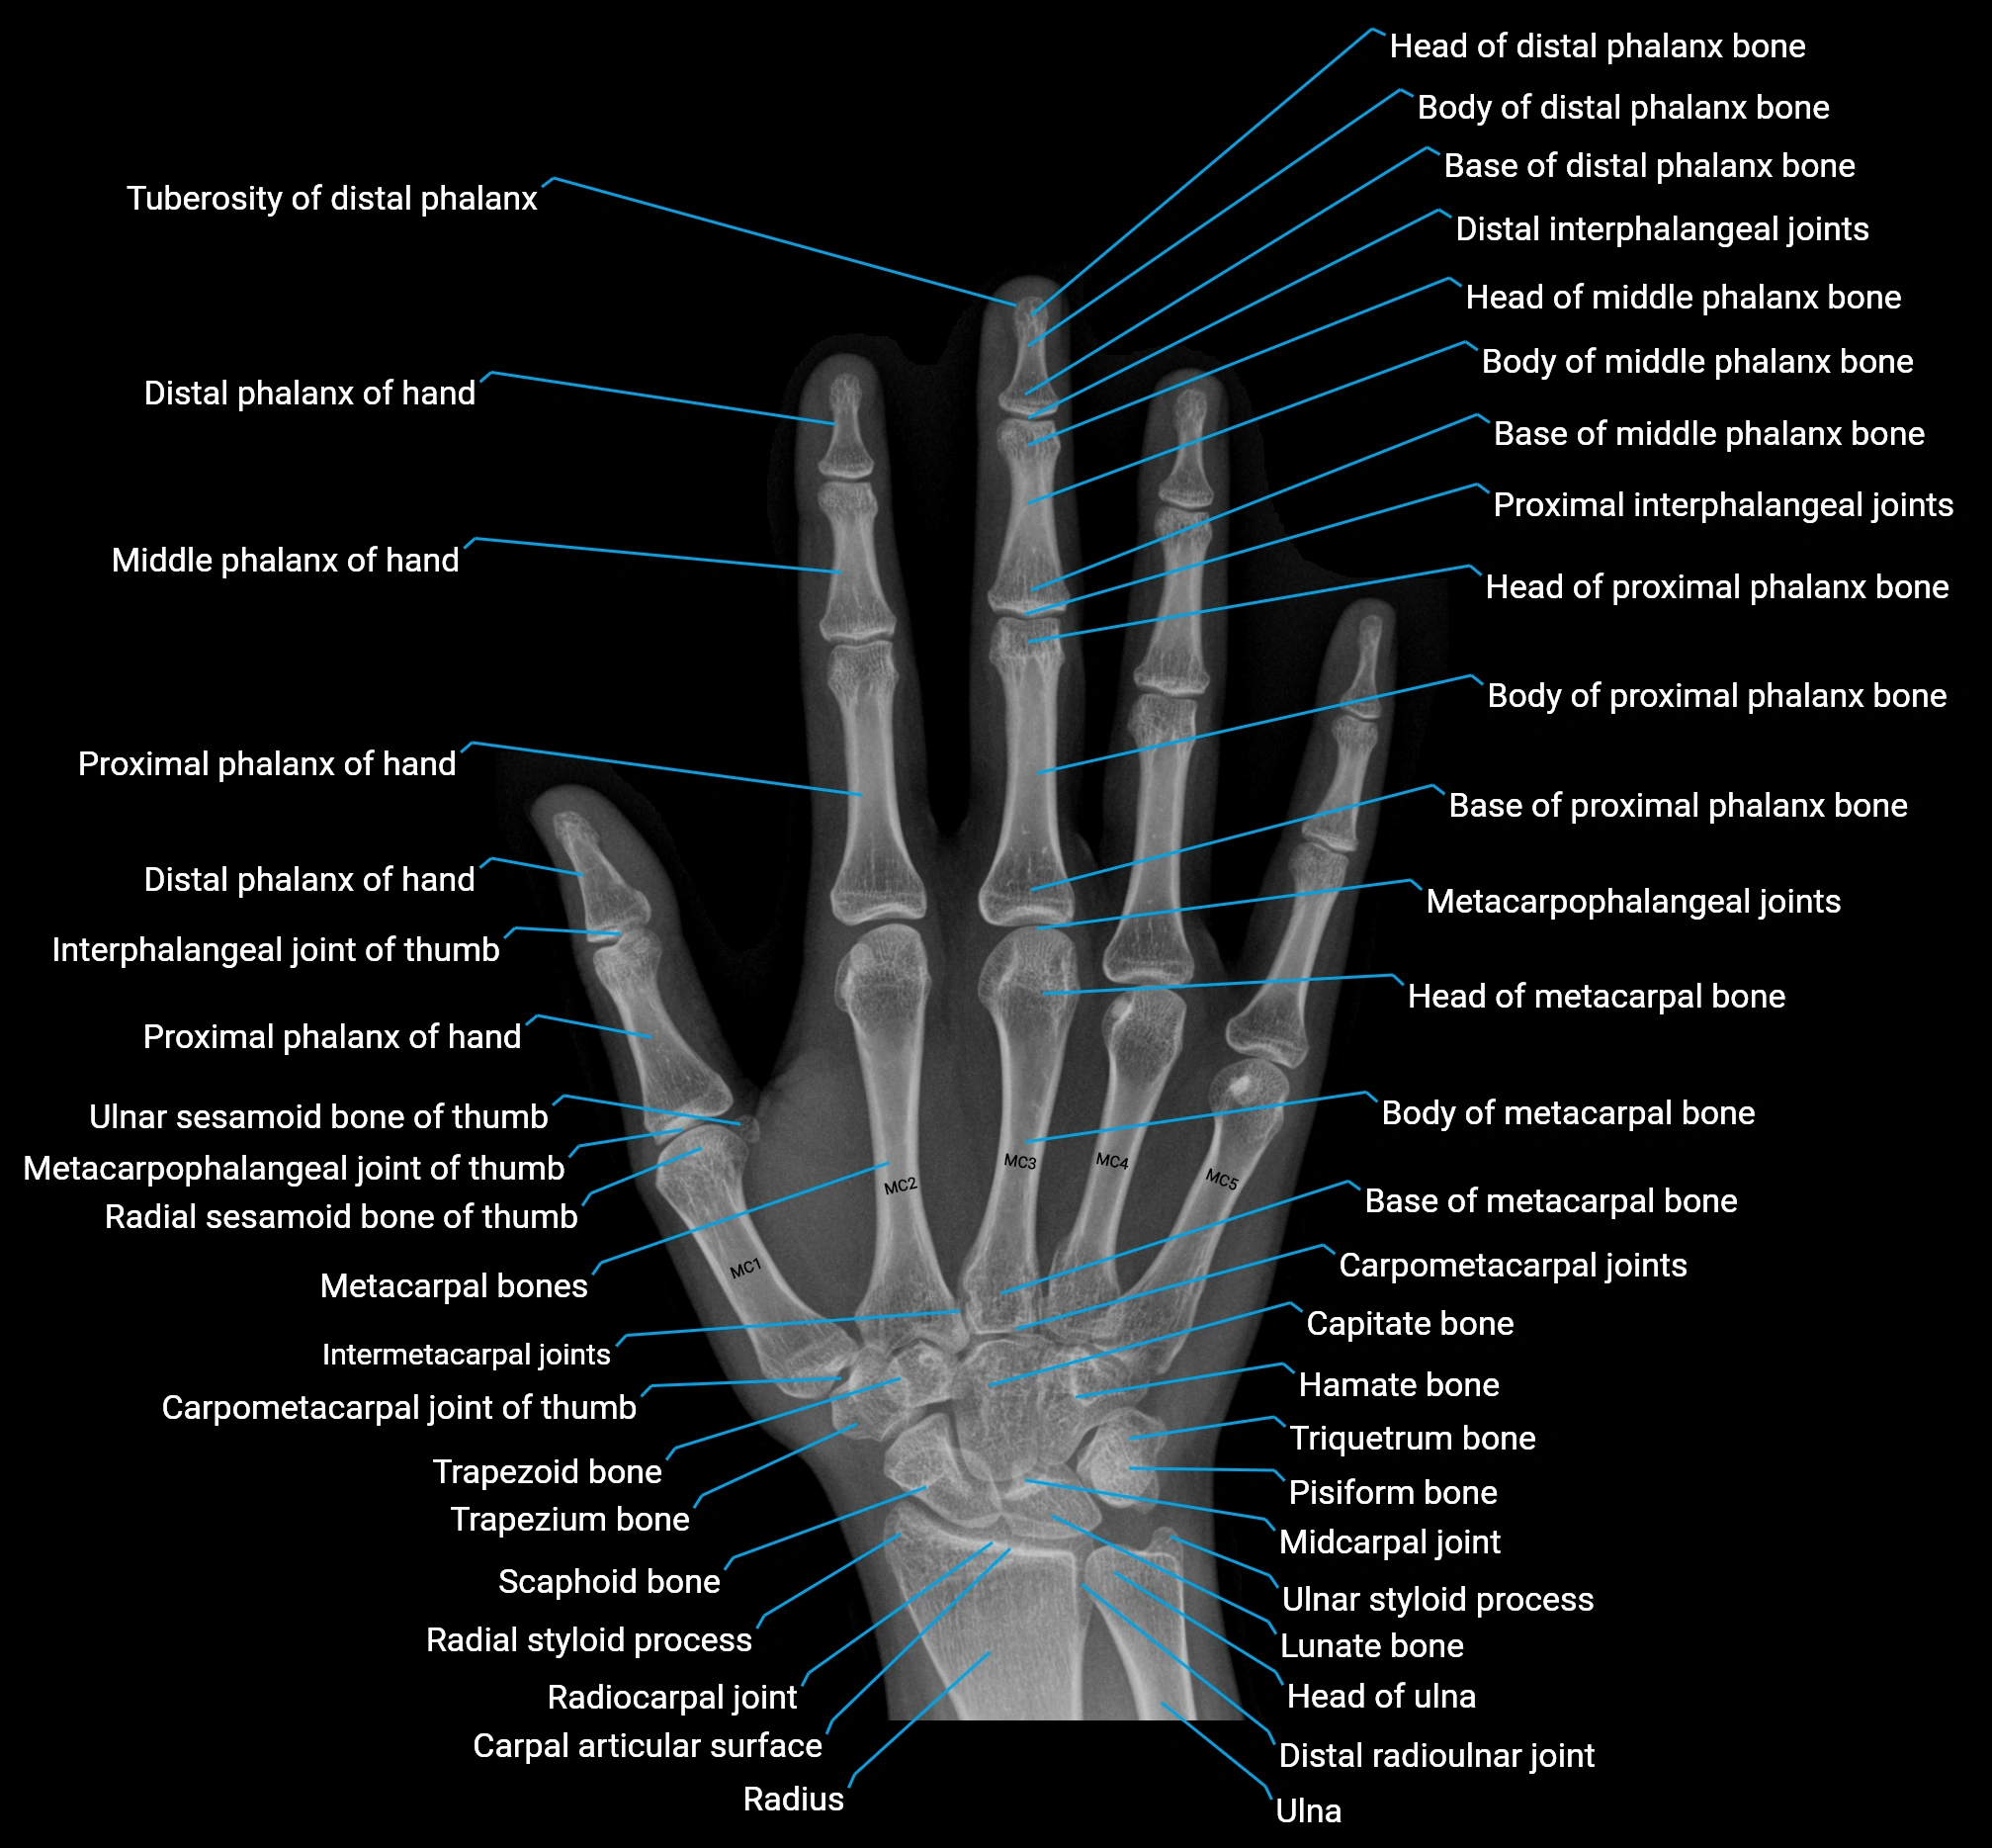

Origin, Course, and Insertion

Origin: From the pisiform bone, the pisohamate ligament, and the tendon of the flexor carpi ulnaris.

Course: Muscle fibers run distally along the ulnar side of the hand, forming a flat tendon near the base of the little finger.

Insertion: Ulnar side of the base of the proximal phalanx of the fifth digit and the extensor expansion of the same finger.

Tendon Attachments

-

The tendon passes along the medial side of the fifth metacarpal and inserts into both the base of the proximal phalanx and dorsal digital expansion.

It may send a slip to the extensor digiti minimi tendon, facilitating combined extension and abduction.

Relations

Superficial: Palmar fascia and skin of the hypothenar eminence

Deep: Flexor digiti minimi brevis and opponens digiti minimi

Medially: Ulnar border of the hand

Laterally: Flexor tendons of the little finger

Proximally: Pisiform and ulnar artery and nerve branches

Distally: Proximal phalanx and extensor expansion of the little finger